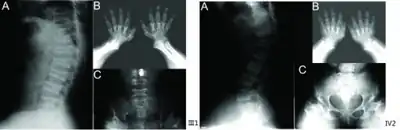

a) Anterior beaking of vertebral bodies b) short metacarpals and phalanges, cone-shaped epiphyses c) scoliosis, small femoral heads, flared metaphyseal borders

Skeletal radiography

Accurate assessment of plain radiographic findings remains an important contributor to diagnosis of pseudoachondroplasia. It is noteworthy that vertebral radiographic abnormalities tend to resolve over time. Epiphyseal abnormalities tend to run a progressive course. Patients usually suffer early-onset arthritis of hips and knees. Many unique skeletal radiographic abnormalities of patients with pseudoachondroplasia have been reported in the literature.[2][7][4]

- Oval shaped vertebrae with anterior beak originating and platyspondyly demonstrated on lateral radiographs of the spine.

- Normal widening of the interpedicular distances caudally demonstrated on anteroposterior radiographs of the dorsolumbar region. This is an important differentiating feature between pseudoachondroplasia and achondroplasia.